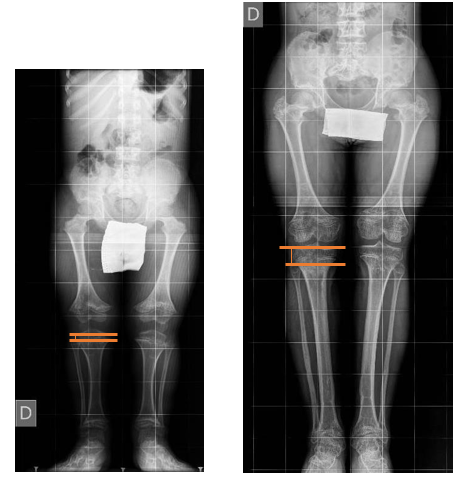

c) The proximal fibular migration (PFM) (Figure 3), comparing the position of the fibular head relative to the tibial plateau on the preoperative radiograph and the radiograph made at the end of the distraction period

Figure 3: Proximal Fibular Migration (PFM) with the Comparison of the Fibular Head and the Tibial Plateau, on a Subject Before and after 15 cm Lengthening Surgery